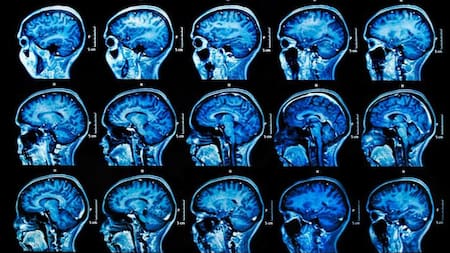

La ELA es una enfermedad progresiva del sistema nervioso que afecta a gente de 40 a 70 años, daña y mata todas las neuronas motoras y atrofia todos los músculos. Destruye las neuronas motoras, es decir, las células encargadas de enviar las señales desde el cerebro y la médula espinal hacia los músculos voluntarios.

Al deteriorarse estas neuronas, los músculos dejan de recibir estímulos, se debilitan y se atrofian. Con el avance del cuadro aparecen dificultades para caminar, hablar, tragar e incluso respirar, aunque en la mayoría de los casos, las funciones cognitivas y los sentidos se mantienen preservados.

La enfermedad se produce por la degeneración de las neuronas motoras del cerebro y la médula espinal, lo que impide que los músculos reciban las señales necesarias para moverse. Entre los primeros síntomas, suelen aparecer: